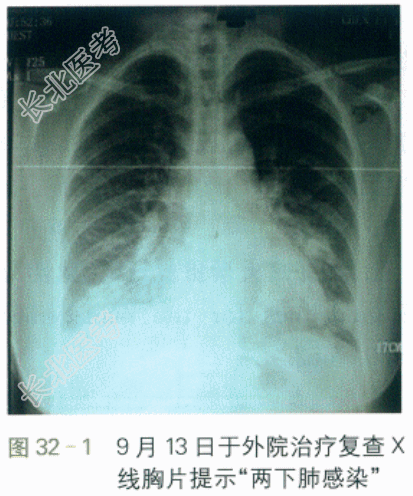

该患者于2009年11月9日起病,咳嗽,发热,体温38.5℃,有畏寒,无寒战。查血WBC7.3×10⁹/L,N89.4%,X线胸片提示未见异常,予头孢呋辛治疗无好转。13日于外院治疗复查X线胸片提示"两下肺感染"(见图32-1),并改用青霉素治疗。14日收住另一医院住院治疗,期间病情加重,出现气急、胸闷,咳铁锈色泡沫痰,每日30口。16日晨出现面色发绀,未吸氧时氧饱和度低至50%,复查床旁X线胸片提示"两肺广泛渗出"(见图32-2)。转入我院,在发热门诊查甲流(+),H1N1(可疑)。患者仍有发热,气急较前加重,予奥司他韦75mg po bid,以及无创呼吸机治疗并转入呼吸科ICU。